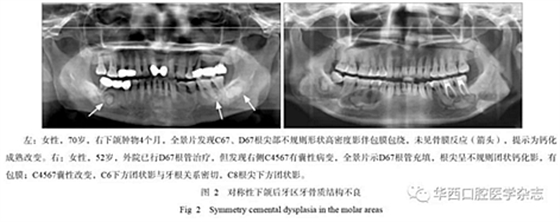

2.3 對稱性的改變

牙骨質(zhì)結(jié)構(gòu)不良可以呈對稱性的發(fā)生,常常發(fā)生于下頜后牙區(qū),影像學(xué)表現(xiàn)為不規(guī)則的高密度影,周圍可以有類似囊腫樣的改變(圖2),臨床醫(yī)生做完根管治療后其囊性改變并未消失,長期追蹤可能會發(fā)現(xiàn)其他改變出現(xiàn)。